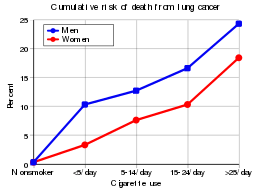

Smoking

Smoking, particularly of cigarettes, is by far the main contributor to lung cancer.[22] Cigarette smoke contains at least 73 known carcinogens,[23] including benzo[a]pyrene,[24] NNK, 1,3-butadiene and a radioactive isotope of polonium, polonium-210.[23] Across the developed world, 90% of lung cancer deaths in men during the year 2000 were attributed to smoking (70% for women).[25] Smoking accounts for about 85% of lung cancer cases.[1]

Passive smoking—the inhalation of smoke from another's smoking—is a cause of lung cancer in nonsmokers. A passive smoker can be defined as someone living or working with a smoker. Studies from the US,[26][27][28] Europe[29] and the UK[30] have consistently shown a significantly increased risk among those exposed to passive smoke.[31] Those who live with someone who smokes have a 20–30% increase in risk while those who work in an environment with secondhand smoke have a 16–19% increase in risk.[32] Investigations of sidestream smoke suggest it is more dangerous than direct smoke.[33] Passive smoking causes about 3,400 deaths from lung cancer each year in the USA.[28]

The population segment most likely to develop lung cancer is people aged over 50 who have a history of smoking. In contrast to the mortality rate in men, which began declining more than 20 years ago, women's lung cancer mortality rates have been rising over the last decades, and are just recently beginning to stabilize.[143] In the USA, the lifetime risk of developing lung cancer is 8% in men and 6% in women.[6]